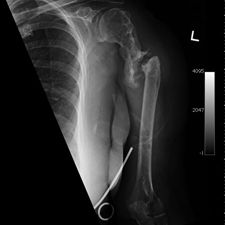

Some time in late May 2010, she presented with movement of the fracture site and was noted that the central area of healing had broken down and was thought that she had a deep infection. She was taken back to theater in mid June 2010 when operation showed that there was no pus. Multiple samples of the fracture site were taken and an external fixator applied with compression of the fragments. Following that, the cultures taken from the wounds showed no growth and no organisms and a biopsy showed no sign of any malignancy or abnormal cells. The fixator became loose and eventually had to be removed. This was done in July 2010 and she was discovered to be going onto a hypertrophic nonunion. Low dose ultrasound treatment of the fracture site was tried to help stimulate healing over the course of a few months but the non union persisted.

She was advised of the need to do some sort of stabilization which is necessary since the use of low-dose ultrasound has not helped in the healing process. She was unwilling to have any further operative intervention and sought further options. Eventually, she agreed to a fourth procedure of intra-medullary nail stabilization of the fracture and had this carried out in April 2011. An intramedullary nail was inserted in an antegrade manner and she has since gone on to heal the fracture site completely and has regained most of the function of the upper limb with no pain.